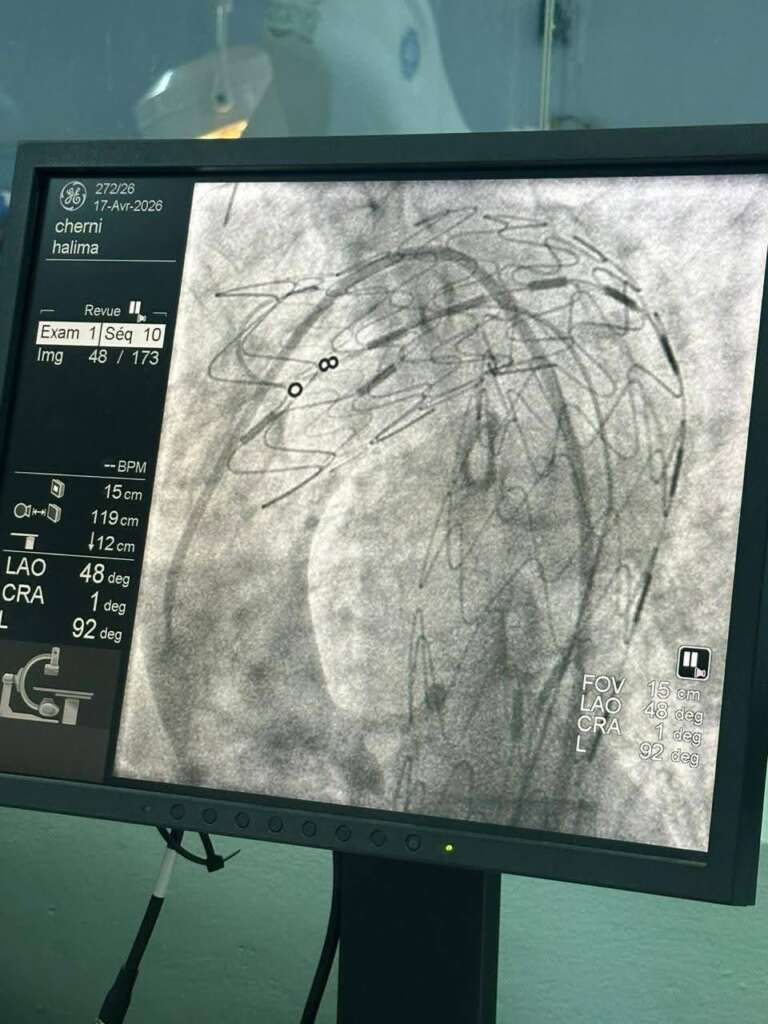

إنجاز طبي رائد بمنزل بورقيبة : نجاح أول عملية لتركيب دعامة للأبهر الصدري

سجّل المستشفى الجهوي بمنزل بورقيبة إنجازًا طبيًا مميزًا، بعد نجاح الفريق الطبي بقسم أمراض القلب في إجراء أول عملية لتركيب دعامة للأبهر الصدري النازل لامرأة تبلغ من العمر 58 سنة، في تدخل دقيق يُعد سابقة على مستوى الجهة.

وقد تم هذا الإنجاز بفضل تكامل جهود الإطارات الطبية وشبه الطبية، وبالتعاون مع فريق جراحة القلب والشرايين بمستشفى عبد الرحمان مامي بأريانة.

ويؤكد هذا النجاح تطور الإمكانيات التقنية بقاعات القسطرة بالمؤسسات الصحية العمومية، وقدرتها على إنجاز تدخلات متقدمة وتقريب الخدمات الصحية ذات الاختصاص العالي من المواطنين.